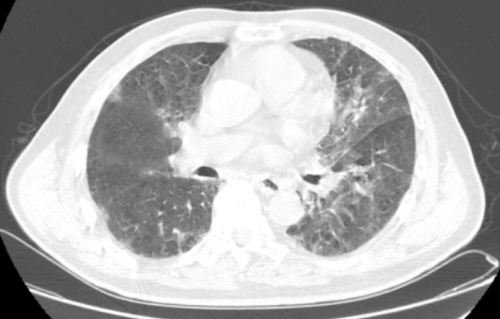

入院时肺部CT(11-07)